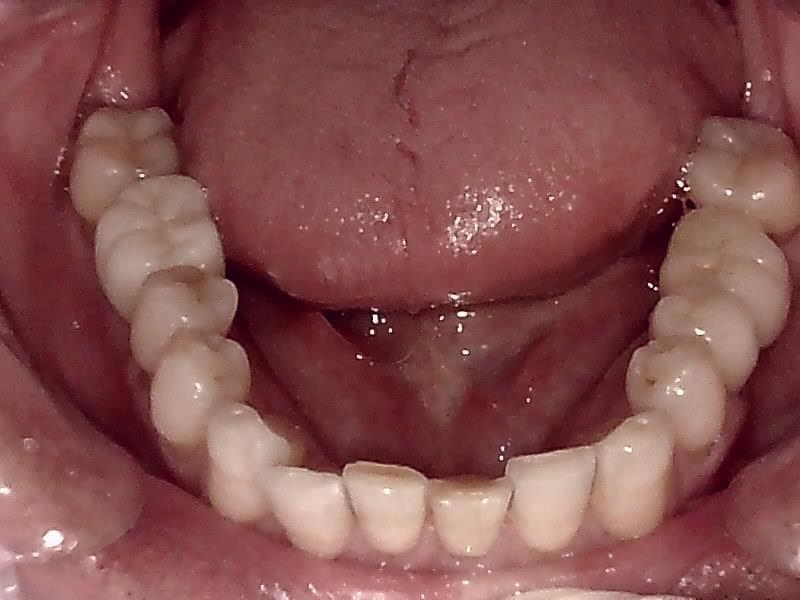

下顎